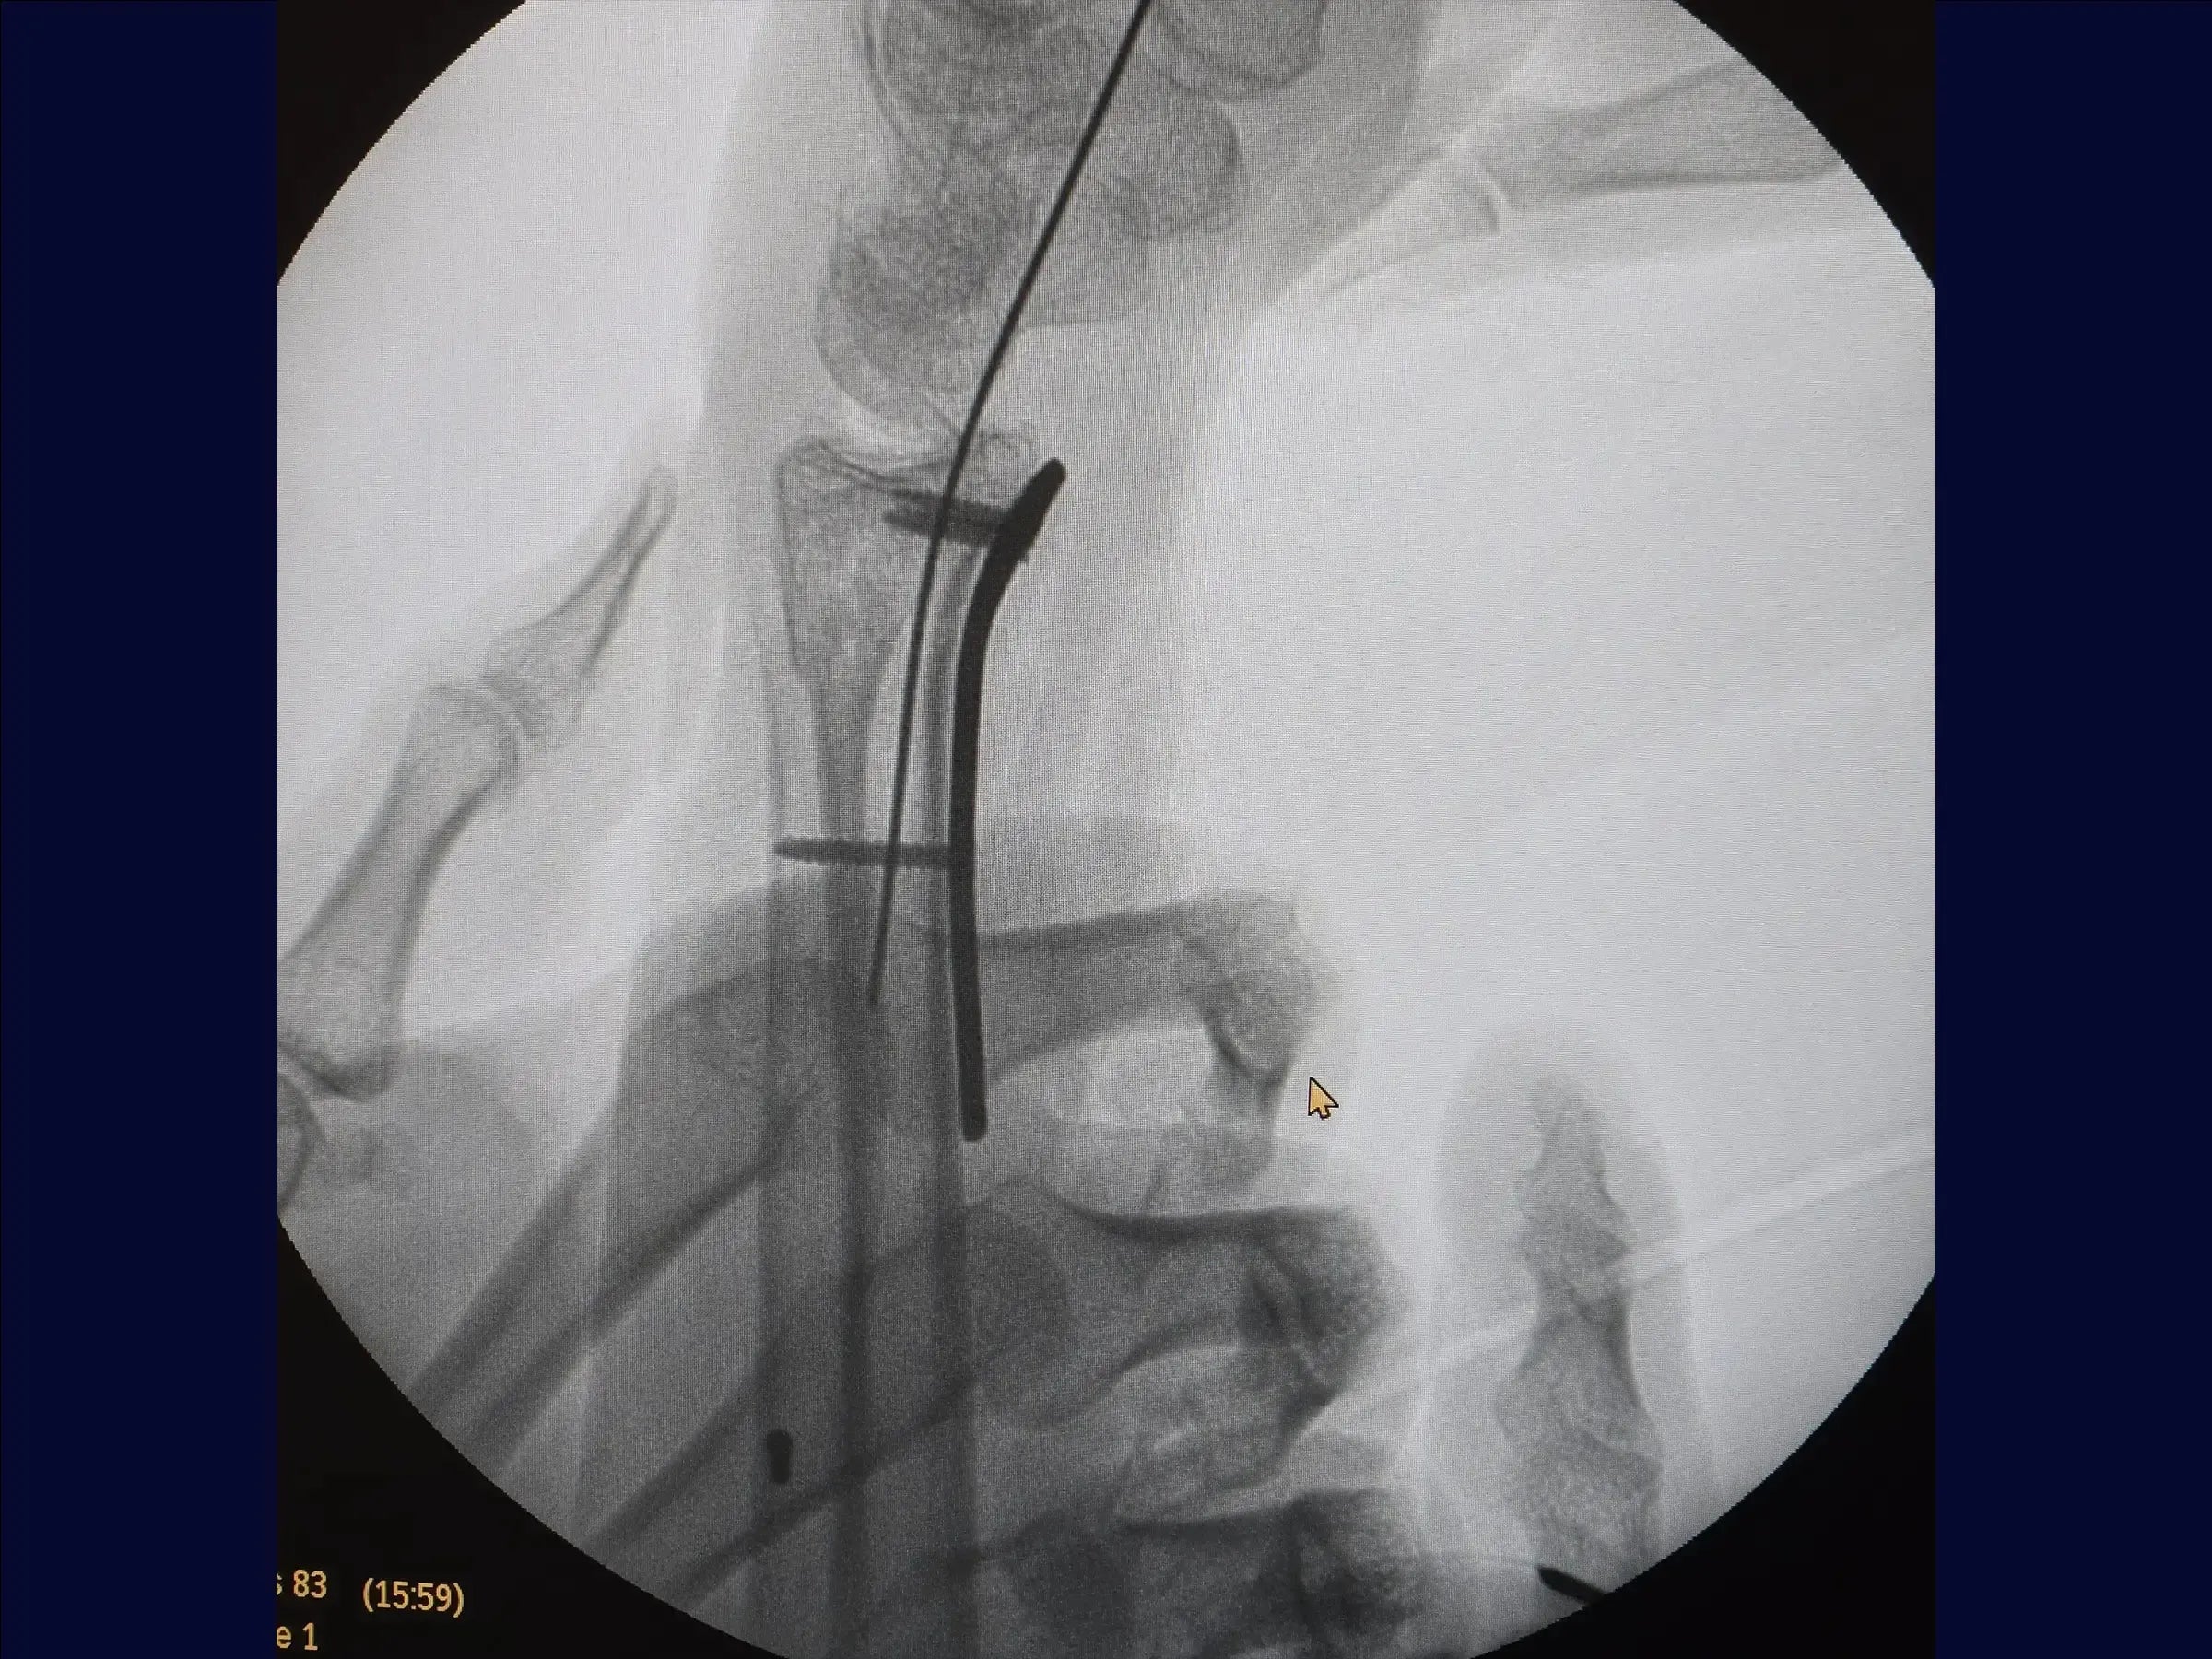

- Preparación y fijación volar: Se reemplaza el retractor, se limpian los vértices de la fractura y se inserta la placa, respetando el límite articular. Se comienza con un tornillo cortical en el orificio oval para compresión. Se utilizan tornillos cortos para fijar el fragmento volar y, con maniobras digitales, tornillos largos estabilizan la superficie dorsal sin necesidad de otro acceso. Los tornillos cortos se reemplazan por tornillos largos (18-20 mm), incluyendo la estiloides, completando la osteosíntesis en los orificios restantes.

- Cierre y resultados finales: Se sutura el pronador cuadrado en línea recta. La reducción es satisfactoria, con una anatomía del radio prácticamente normal. Se realiza un cierre cutáneo para obtener un resultado satisfactorio.